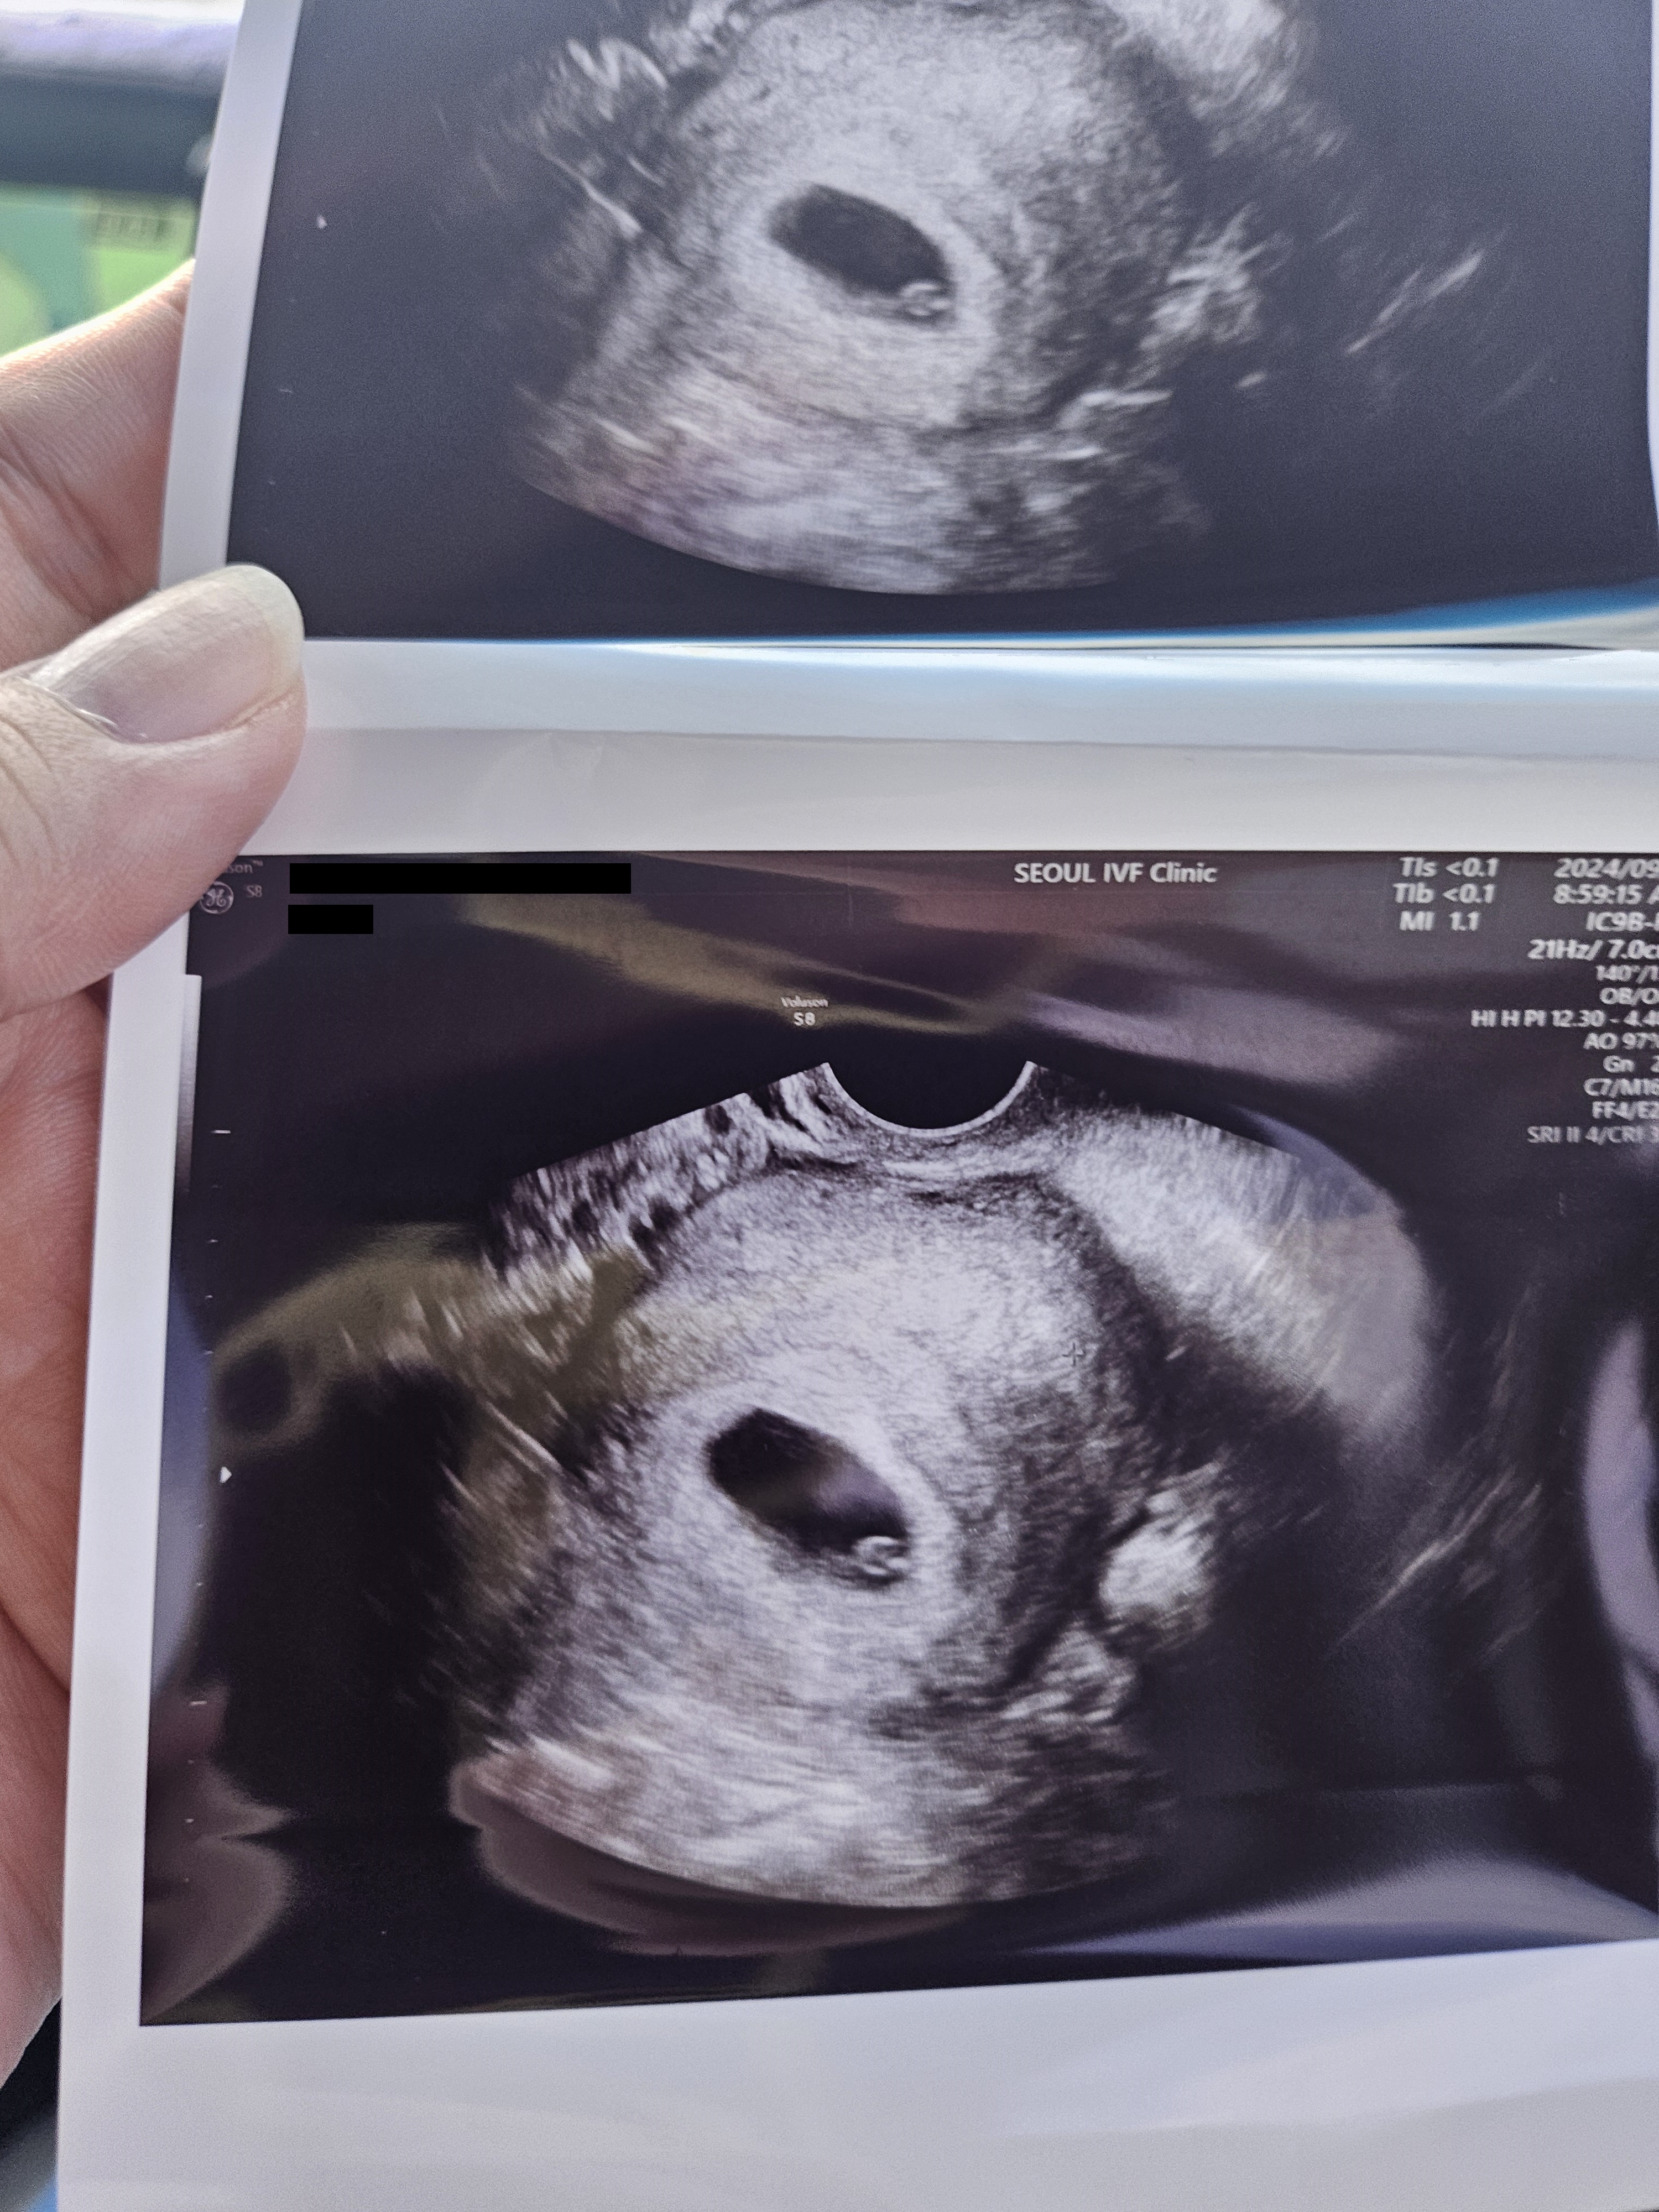

| 가슴 떨리는 임신 이야기를 공유해 주세요. | 저는 동결 3차 때 임신에 성공했어요 중간에 임신했다가 유산도 했지만 다시 진행하였고 이식 후 다시 한번 두 줄을 보았습니다. |